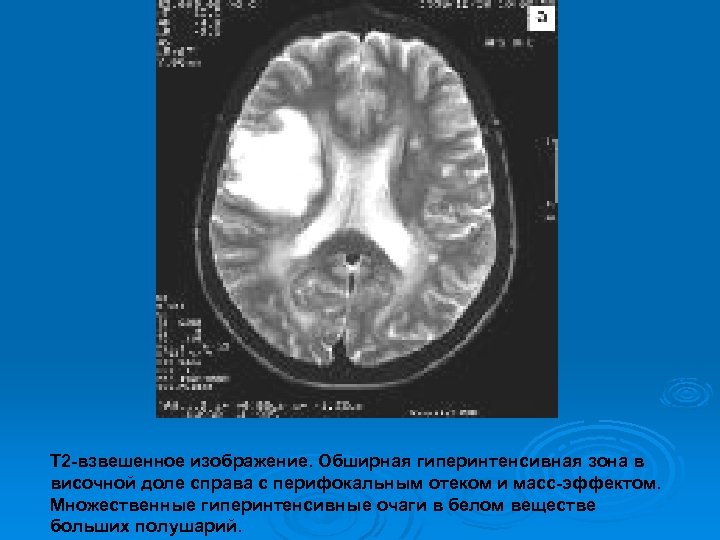

Изменения МРТ на фоне гормональной терапии

Т 2 -взвешенное изображение. Обширная гиперинтенсивная зона в височной доле справа с перифокальным отеком и масс-эффектом. Множественные гиперинтенсивные очаги в белом веществе больших полушарий.